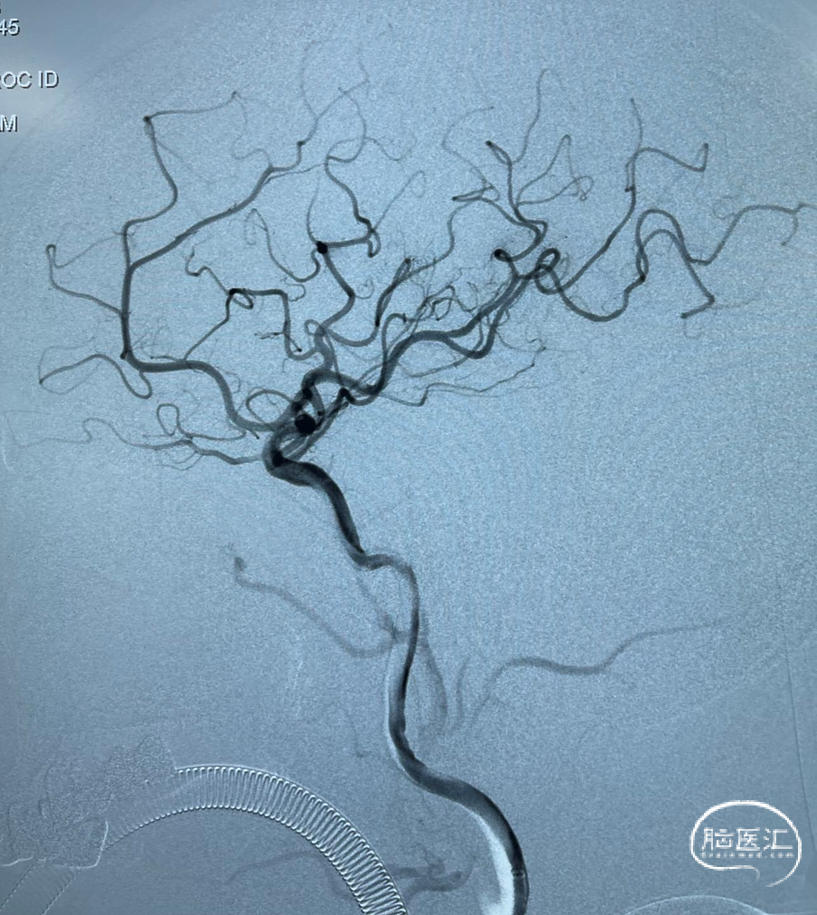

术后DynaCT,有少量造影剂外渗。予速尿针、白蛋白针、甘露醇针脱水预防脑水肿,阿司匹林肠溶片、抗血小板,强化他汀治疗。

术后复查头颅CT:无明显出血等表现。